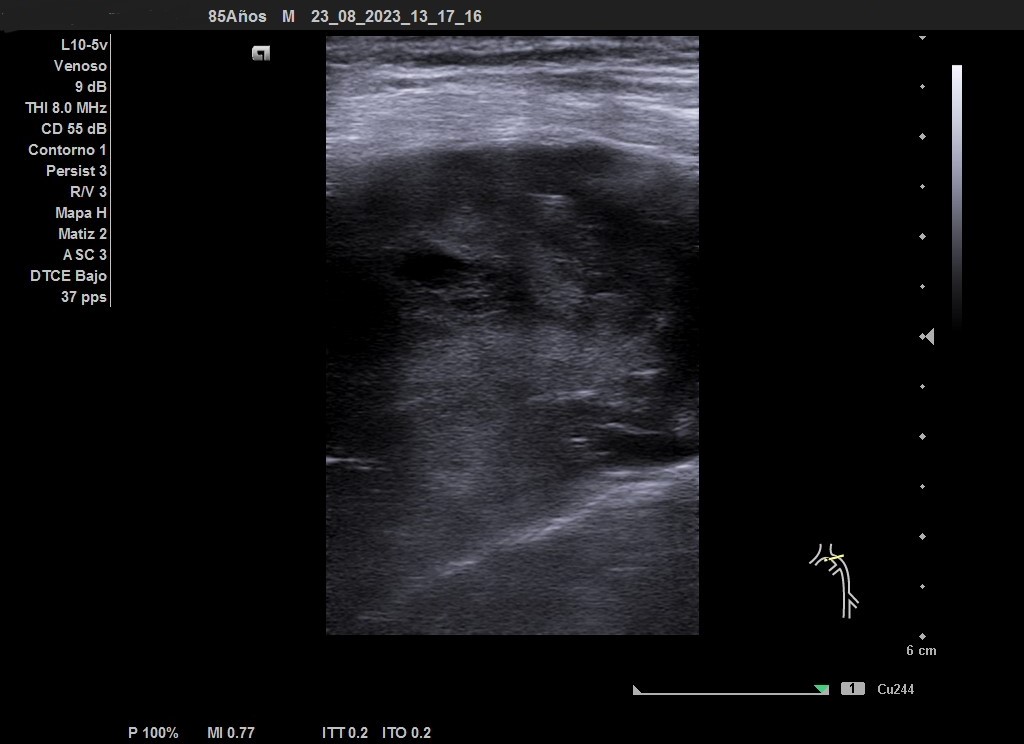

Ecografía venosa: venas femorales y poplíteas permeables. A nivel inguinal se observa imagen heterogénea, mal definida, sospechosa de malignidad.